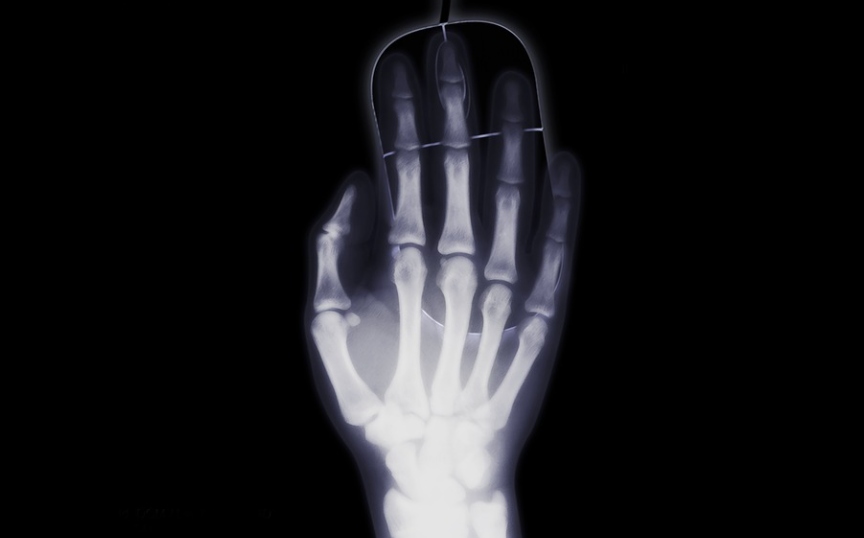

Рентген